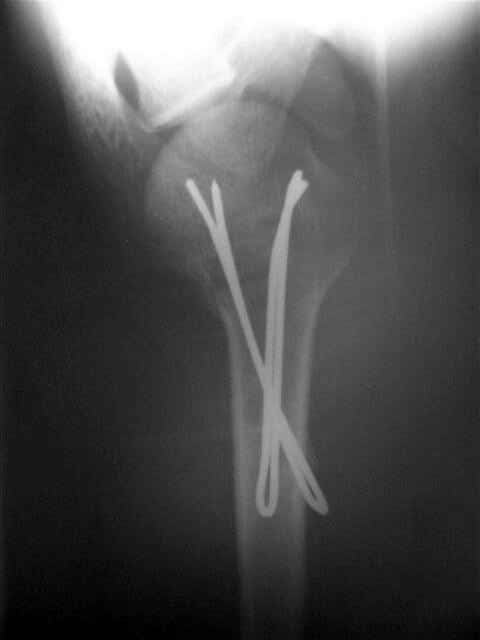

Женя, а как ты водишь спицы, в смысле, как делаешь входное отверстие, и как в него проводишь V-спицу? А то о дна из спиц, та, у которой не дошла до головки одна палочка буквы V, как-то выглядит на рентгенограмме, как будто или через очень большое отверстие введена, или каждая половинка через отдельные отверстия.

Мне кажется, проблема в том, что не все концы спиц зашли в головку, и зашедшие - недостаточно далеко прошли.

Спицы провожу по передней и задней поверхностям плечевой кости через 4,5 мм отверстия на разных уровнях.

Уточни - обе части буквы V вводишь в одно отверстие? А то по снимкам выглядит, что в разные.

V-спица проводится через 4,5 мм отверстие. Видимо, из-за разной длины вторая половина спицы *пролетела* мимо отверстия, что и привело к вторичному смещению костных фрагментов.